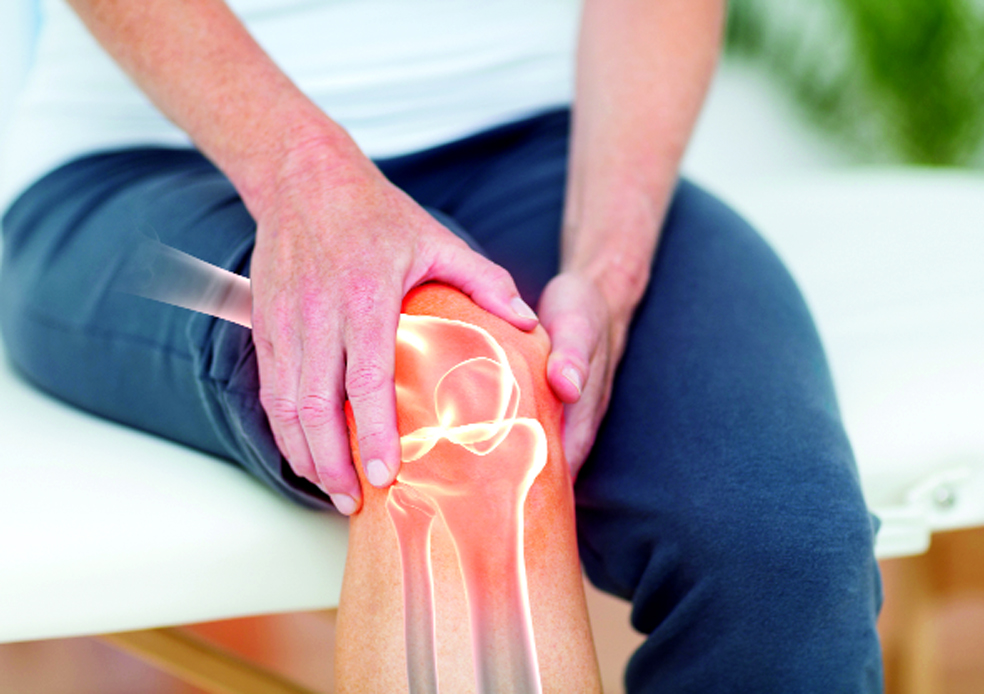

Sports Injury